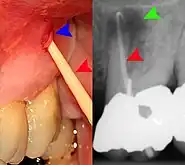

Sometimes the symptoms reported in the history are misleading and point the examiner to the wrong area of the mouth. For instance, sometimes people may mistake pain from pulpitis in a lower tooth as pain in the upper teeth, and vice versa. In other instances, the apparent examination findings may be misleading and lead to the wrong diagnosis and wrong treatment. Pus from a pericoronal abscess associated with a lower third molar may drain along the submucosal plane and discharge as a parulis over the roots of the teeth towards the front of the mouth (a "migratory abscess"). Another example is decay of the tooth root which is hidden from view below the gumline, giving the casual appearance of a sound tooth if careful periodontal examination is not carried out.

Any tooth that is identified, in either the history of pain or base clinical exam, as a source for toothache may undergo further testing for vitality of the dental pulp, infection, fractures, or periodontitis. These tests may include:[12]: 10–19

- Pulp sensitivity tests, usually carried out with a cotton wool pledget sprayed with ethyl chloride to serve as a cold stimulus, or with an electric pulp tester. The air spray from a three-in-one syringe may also be used to demonstrate areas of dentin hypersensitivity. Heat tests can also be applied with hot Gutta-percha. A healthy tooth will feel the cold but the pain will be mild and disappear once the stimulus is removed. The accuracy of these tests has been reported as 86% for cold testing, 81% for electric pulp testing, and 71% for heat testing. Because of the lack of test sensitivity, a second symptom should be present or a positive test before making a diagnosis.

- Radiographs utilized to find dental caries and bone loss laterally or at the apex.

- Assessment of biting on individual teeth (which sometimes helps to localize the problem) or the separate cusps (may help to detect cracked cusp syndrome).

Less commonly used tests might include trans-illumination (to detect congestion of the maxillary sinus or to highlight a crack in a tooth), dyes (to help visualize a crack), a test cavity, selective anaesthesia and laser doppler flowmetry.